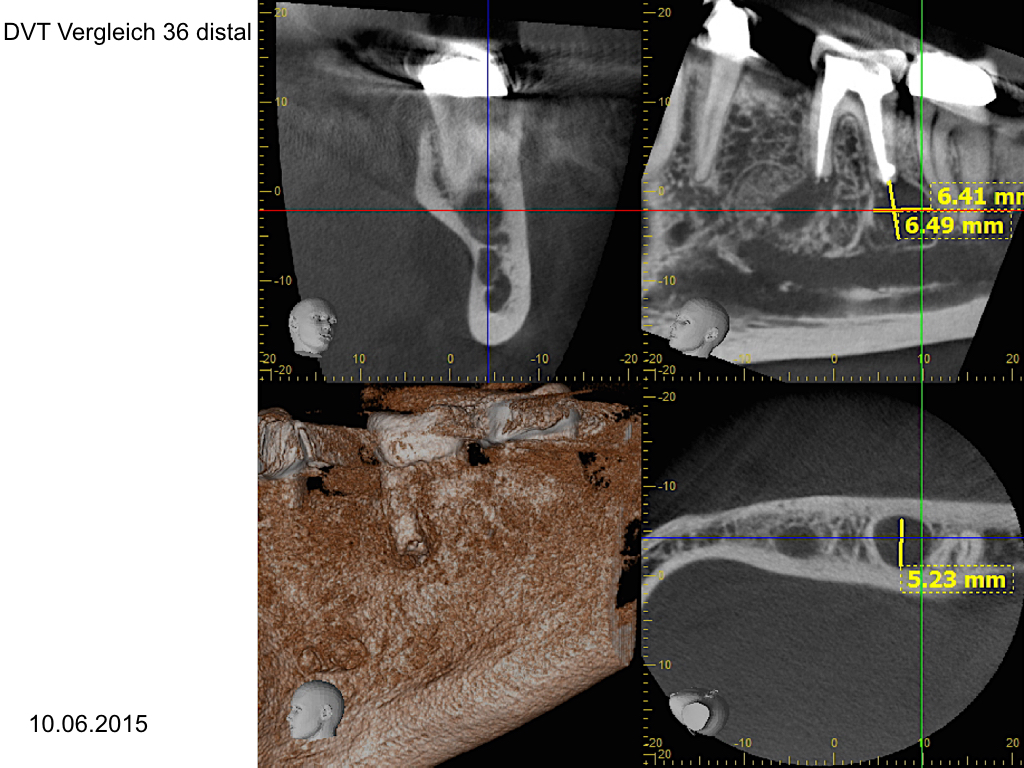

WS_Zy UK.007

Eine Fallvorstellung (2)